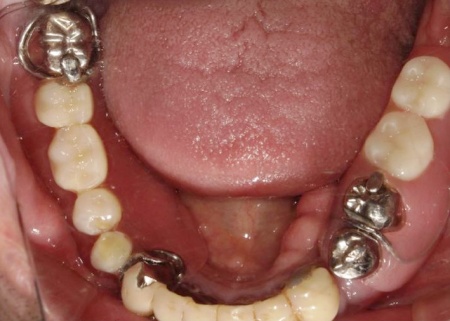

拝見したところ、すでに複数の歯が欠損しており、上下顎には入れ歯が装着されていました。

上前歯は、装着していたブリッジ(複数の人工歯を連結した被せ物)が外れてしまっているため、食事や会話に大きな支障をきたしています。

残っている歯についても、長期間の負担により状態が悪く温存が困難な歯や、細菌感染した神経を取り除いてから薬を詰める根管治療が必要な歯がありました。

また、従来の入れ歯は残っている歯にバネをかけて支えるため、その歯に過度な力がかかり続け、将来的にはその歯も失ってしまうリスクが高い状況です。